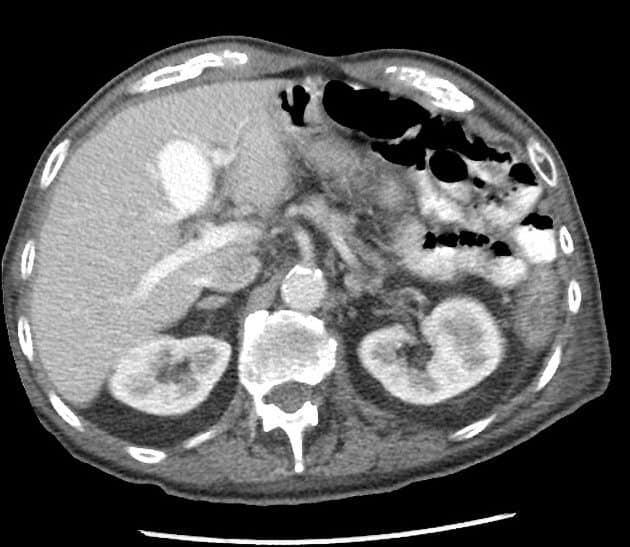

Phình TM cửa

» Thông tin: Nam giới – 90 tuổi.

» Lâm sàng: Kiểm tra sức khỏe.